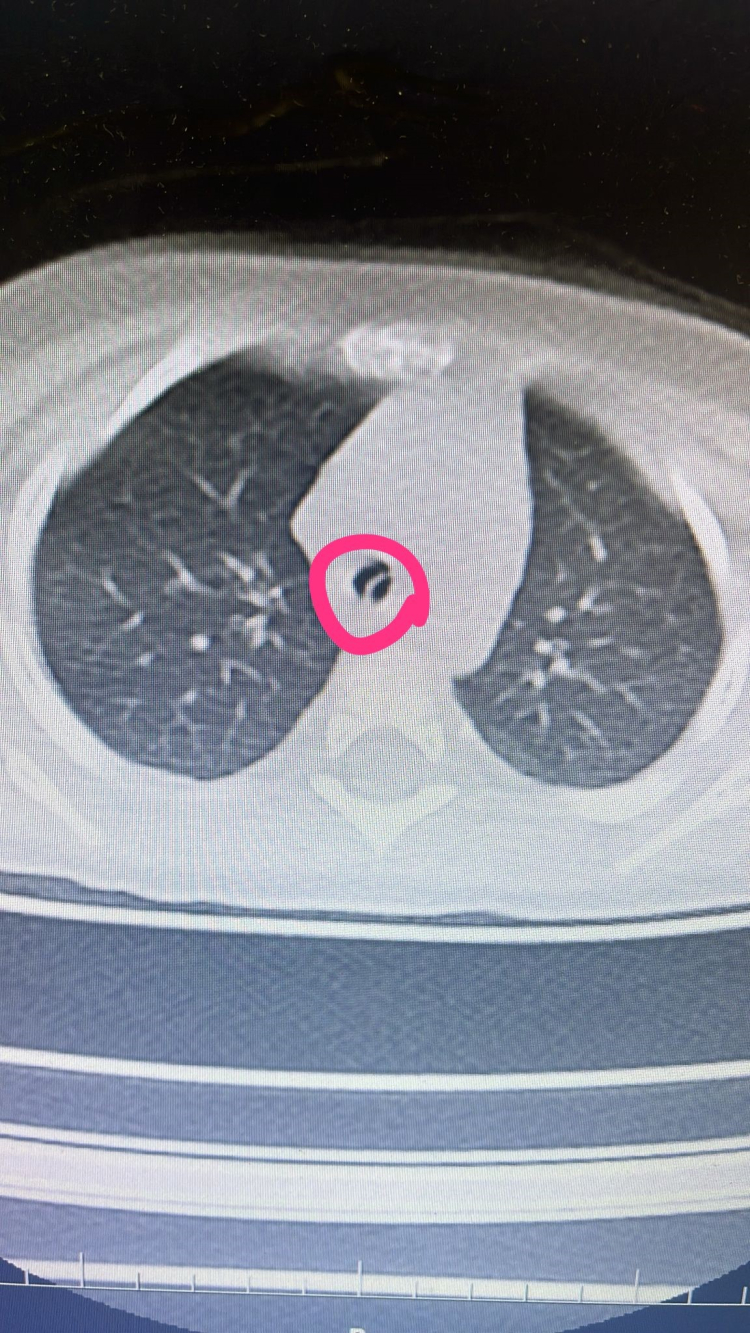

Yapılan tetkiklerde 9 aylık Mine Kavak'ın yuttuğu çekirdek kabuklarından 2-3 tanesinin dik bir şekilde akciğerine saplandığı belirlendi. Batman Eğitim ve Araştırma Hastanesi Çocuk Cerrahisi Doktor Selim Özkaya tarafından ameliyata alınan 9 aylık Mine bebek, bronkoskopi işlemi ile ağız yoluyla ince, ince metal bir kamera tüpü ile akciğerlerine girilerek akciğere saplanan kabuklar çıkartıldı.